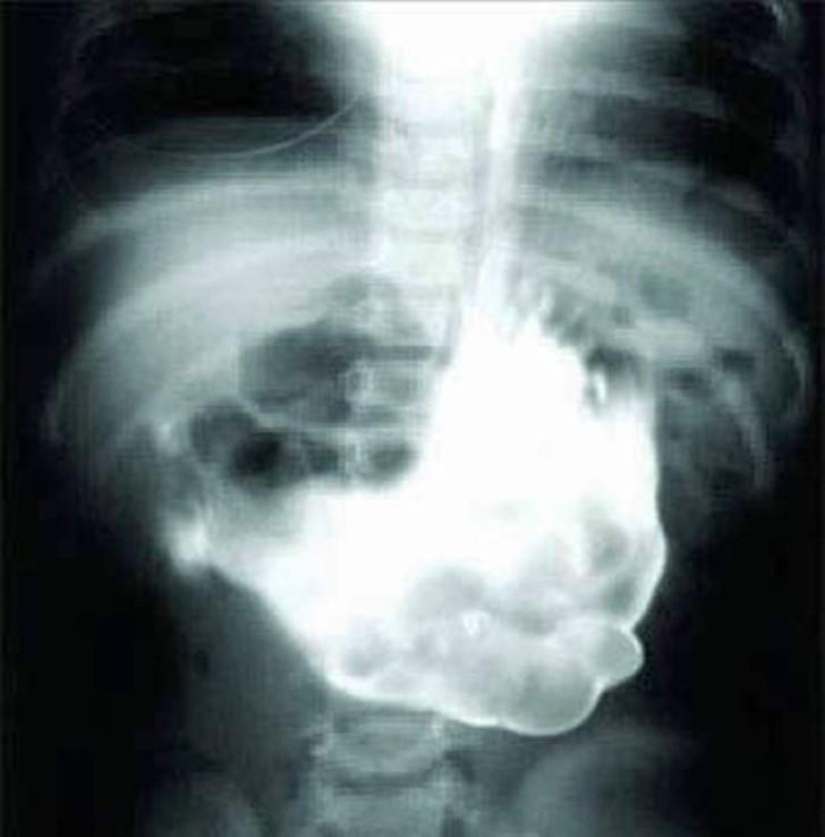

Bulbo.